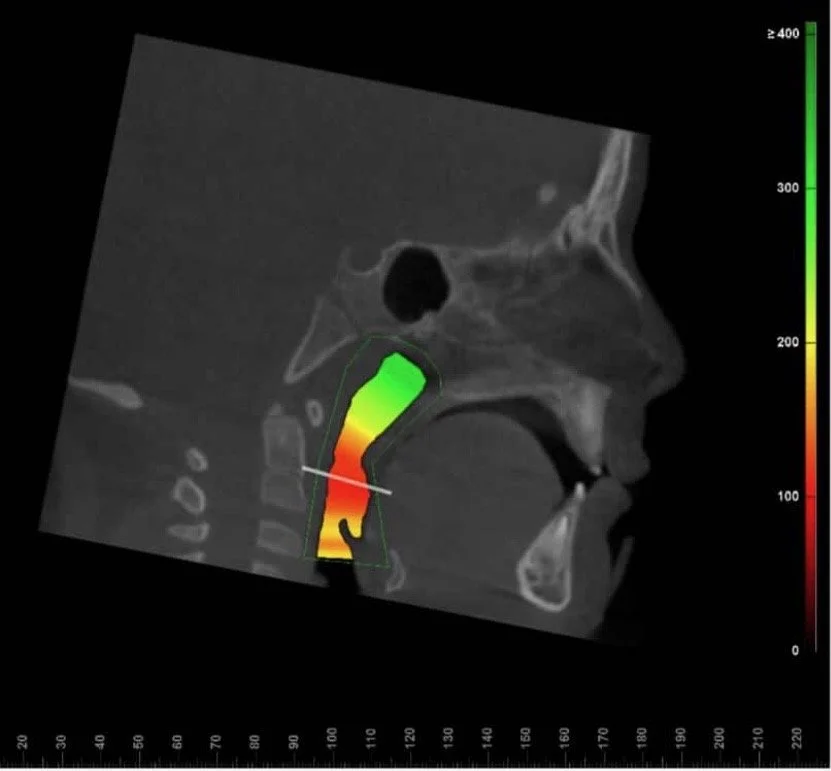

A comprehensive evaluation includes understanding your child’s sleep environment, craniofacial structure, and oral function. To gain a complete picture, Dr. Nez may use the following diagnostic tools:

•    Imaging (Cone Beam Computed Tomography – CBCT)